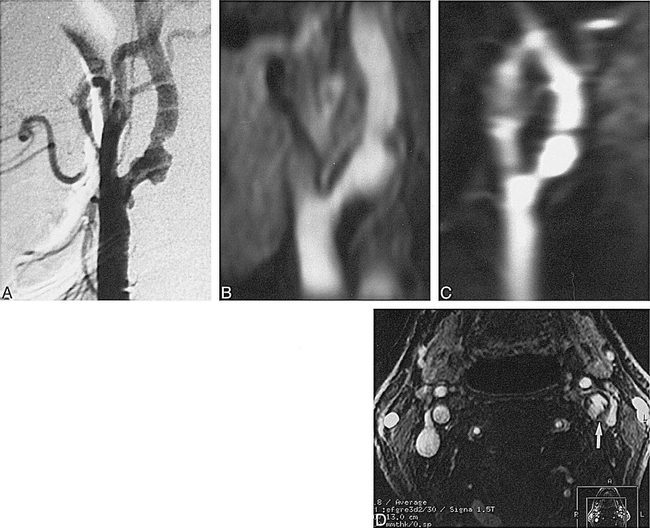

Severe stenosis of the left internal carotid artery in a 79-year-old man.

A–D, IADSA image (lateral view) (A); partial MIP image of second-phase (axial) 3D contrast-enhanced MR angiogram (B); partial MIP image of the first-pass (coronal) 3D angiogram (C); source image of the second-phase (axial) 3D angiogram (D). Irregular forms of stenosis are well visualized on axial view; however, coronal view fails to show details of the stenotic lesions, mainly because of low spatial resolution in the anteroposterior direction. A source image of second-phase (axial) 3D angiography clearly shows irregular plaque (arrow, D).